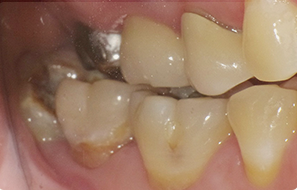

本院為40年 口腔外科專業診所,主攻”安全、無痛”、專拔高風險(牙根與神經交錯或緊貼)、高難度、深度阻生智齒手術。

外面一顆要拔兩個小時,本院一顆十分鐘